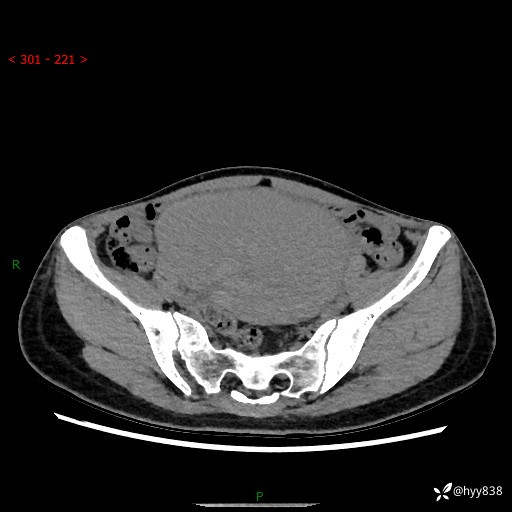

【患者信息】:女,50岁

【主诉】:外院超声发现腹盆肿块,为进一步诊治来我院,门诊已“盆腔肿块”收入院。

腹盆CT平扫+增强

【临床诊断】:盆腔肿瘤